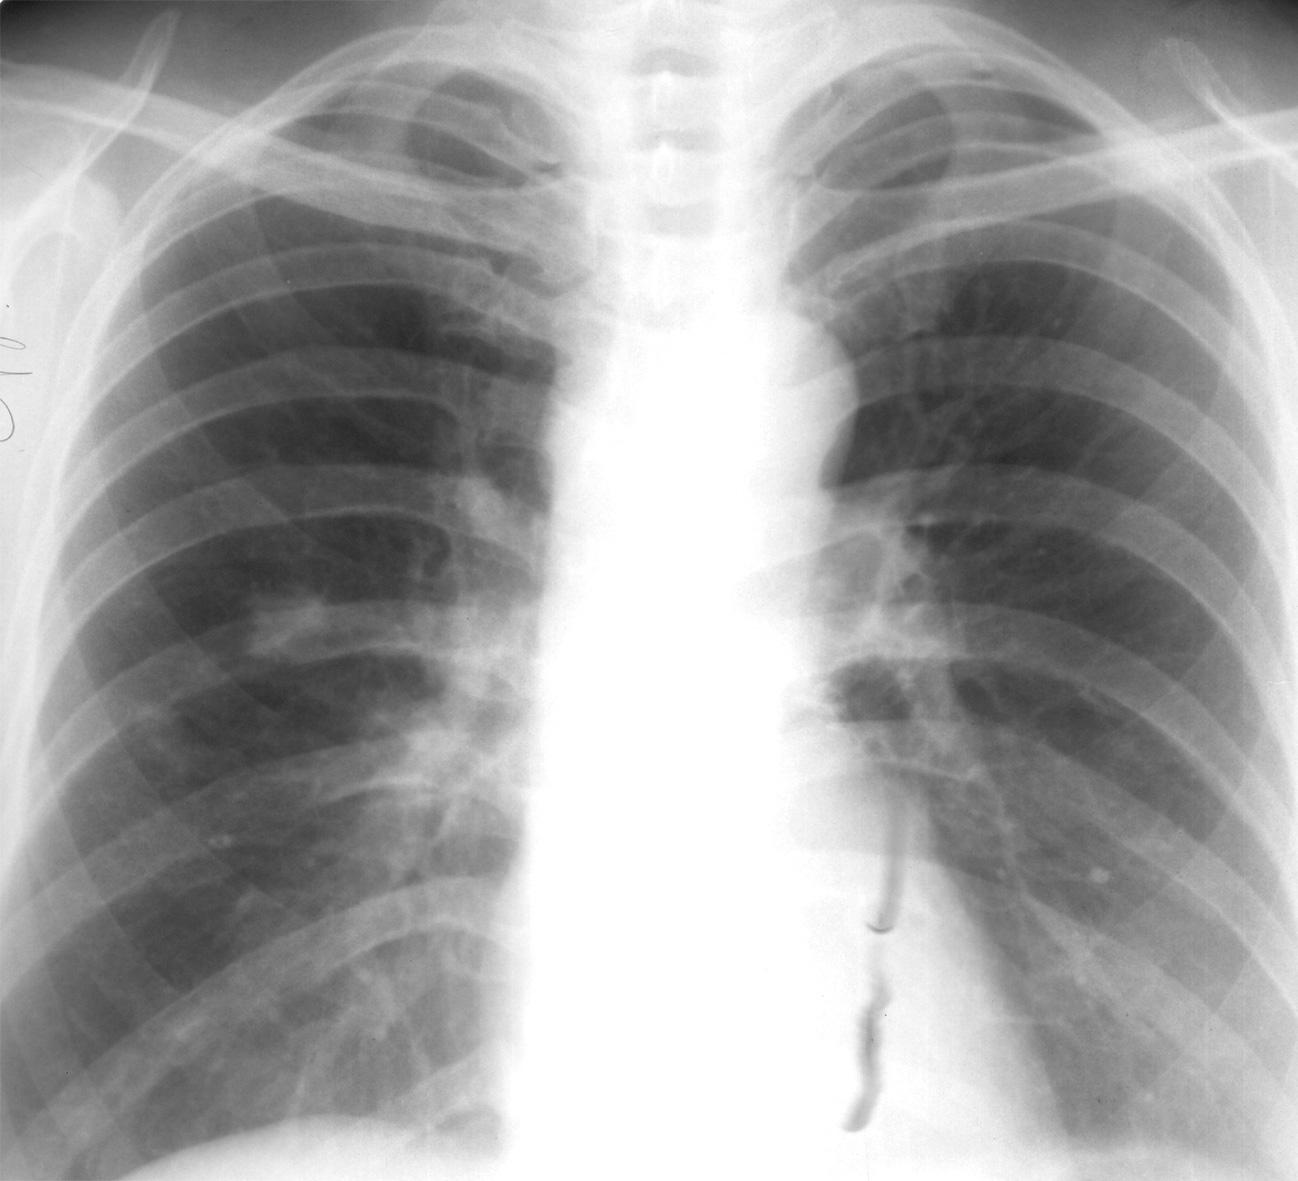

Для точного определения аортальной недостаточности врачу необходимо проанализировать результаты следующих исследований:

- рентгенография грудной клетки;